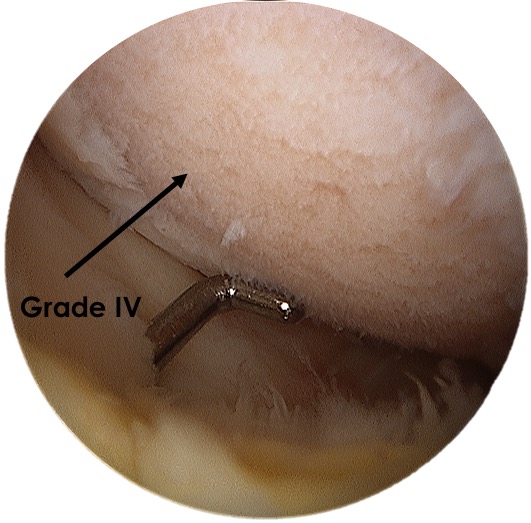

Cartilage Damage를 판별하는 기준에는 Outerbridge classification 을 사용합니다.

MRI 보다는 관절경을 통해 Intra-op status 에서 퇴행성 단계를 평가하는 경우가 많습니다.

제일 중요한 Grade 입니다. Grade 1 의 경우 softening이나 swelling 정도이며 2부터 Partial, 3은 Fissuring, 4부터는 Subchondral bone 이 노출되었을때 4라고 표현하게 됩니다. K-L grade 와 다르게 좀더 디테일하게 관절의 손상 정도를 표현할 수 있습니다.